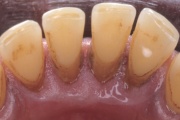

Krooniline parodontiit

Krooniline parodontiit on mikroobide poolt põhjustatud hammaste tugikudede põletik, mille tulemusena tekib progresseeruv alveolaarluu (nähtav röntgenograamil) ja periodontaalligamendi destruktsioon, igemetaskute moodustumine, igeme retsessioon või mõlemad kahjustused kombineeritult. Loe edasi »

- igemepiir on taandunud (3)

- hamba kinnitussidemete kadu (3)

- puudulik suuhügieen (5)

- igemepealne hambakivi (5)

- igemealune hambakivi (4)